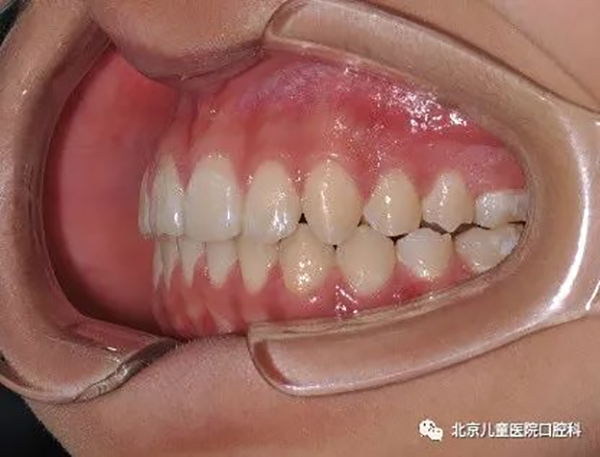

4、前移磨牙,关闭间隙。

治疗前

治疗中

治疗后